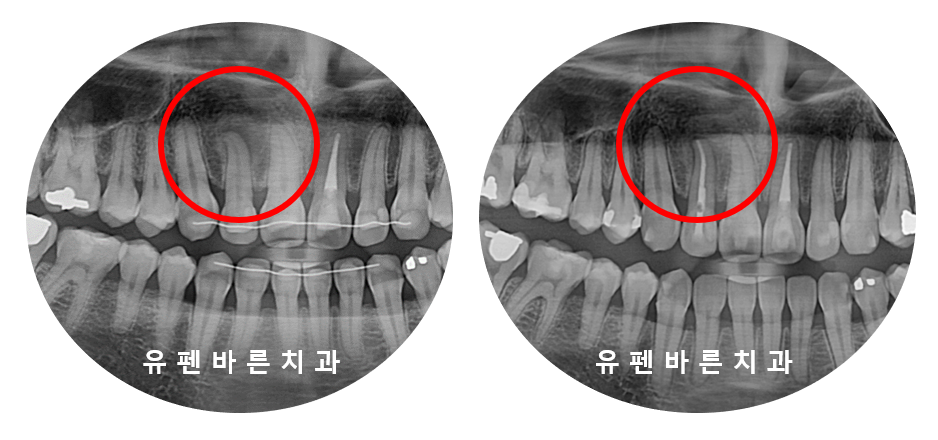

엑스레이를 찍어보니

특정적으로 많이 닿고 있는 부분에

뿌리 끝 염증이 생겨 있었어요 T_T

신경료를 마치고 나니

확연히 염증의 크기가 줄어들었습니다^^